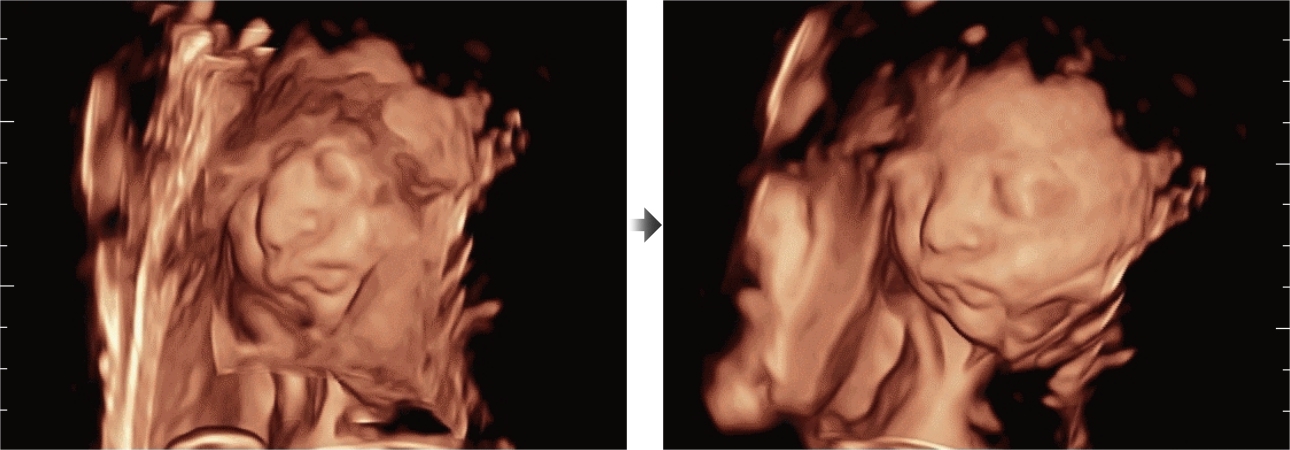

Desde su creaciÃģn, Mindray no ha dejado de explorar nuevas maneras de mejorar la fiabilidad del diagnÃģstico. Gracias a ZONE Sonography?, la tecnologÃa mÃĄs revolucionaria, la nueva plataforma ZST+ del Resona 7 eleva la calidad de imagen de ultrasonido mediante la adquisiciÃģn de zonas y el procesamiento de datos de canal.